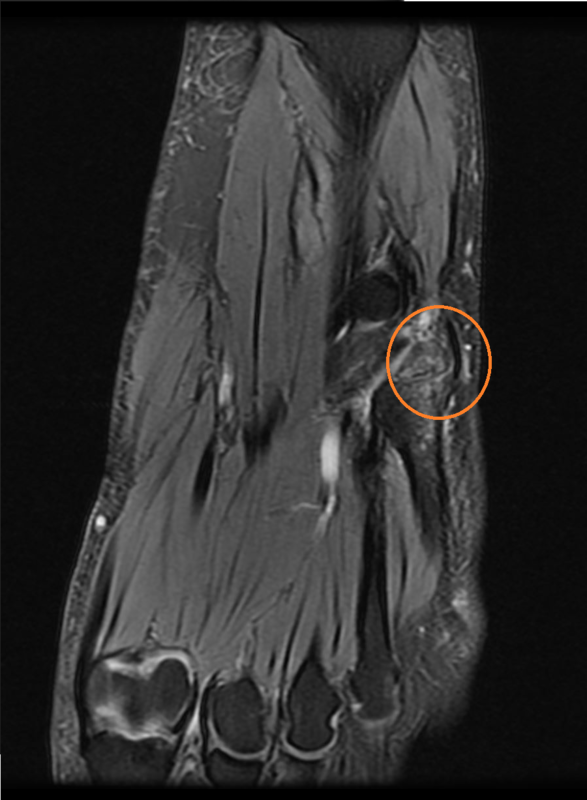

画像検査(MRI)

赤く囲んだ部分が骨折しているところです。骨折している周囲が画像では白く映り、炎症が起きている。